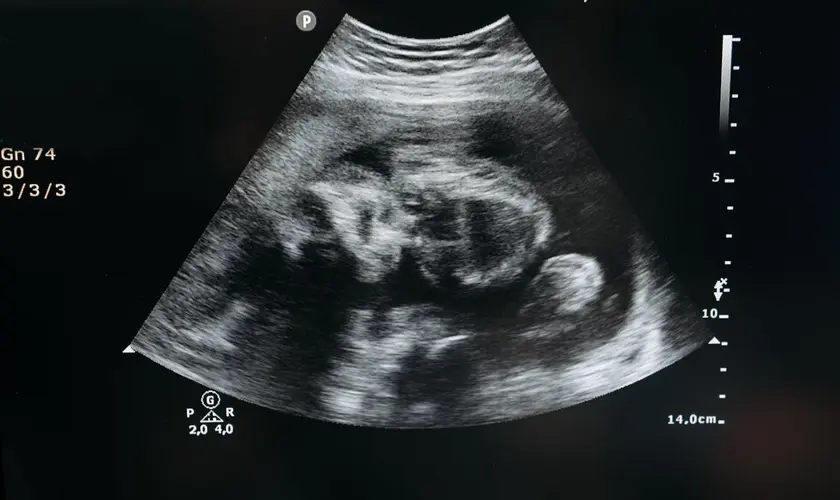

A Câmara dos Representantes de Porto Rico aprovou um projeto de lei que reconhece a criança ainda no ventre como pessoa natural no Código Civil.

A nova legislação estabelece que o ser humano em desenvolvimento no útero – em qualquer fase da gestação – passa a ser reconhecido legalmente como “pessoa natural”.